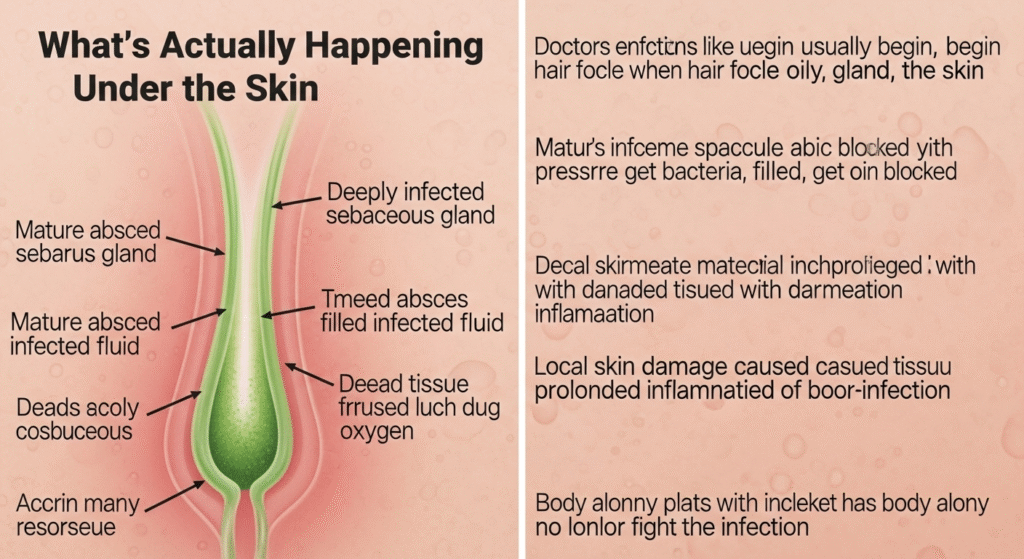

🧠 What’s Actually Happening Under the Skin?

Doctors explain that infections like this usually begin when a hair follicle or oil gland becomes blocked. Once bacteria get trapped, pressure builds beneath the skin, creating a painful abscess.

In this case, specialists believe the condition may involve:

- A deeply infected sebaceous gland

- A mature abscess filled with infected fluid

- Dead tissue forming due to lack of oxygen

- Local skin damage caused by prolonged inflammation

The green coloration suggests infected material mixed with damaged tissue — a clear warning sign that the body alone can no longer fight the infection.